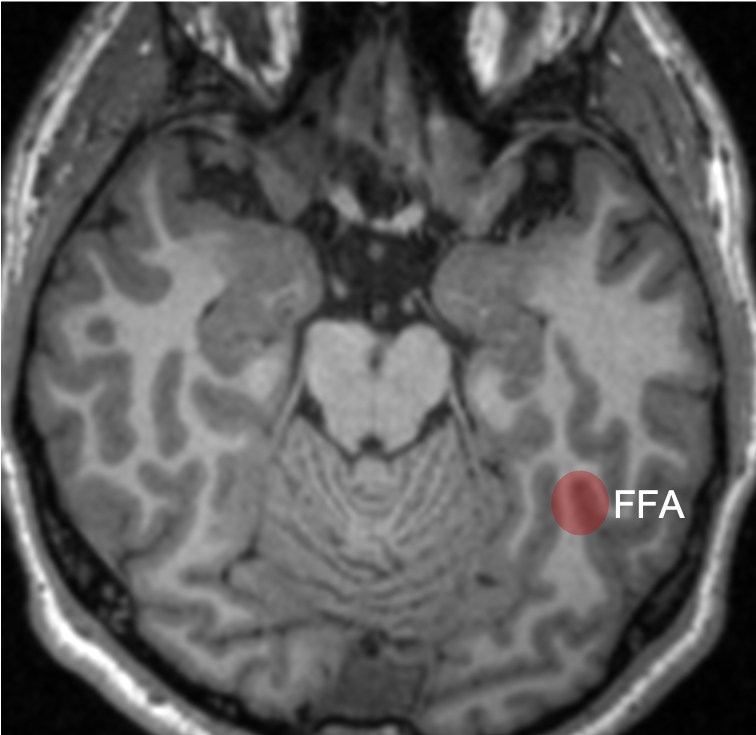

The lingual gyrus is involved in holistic visual and word processing, encoding visual memories, imagery, and dreaming. The ganglioglioma in the shown case is centered in the lingual gyrus.

Fusiform g is just lateral to lingual g on the inf surface of temporal lobe, separated by collateral sulcus. It& #39;s medial to the ITG, separated by ITS. Involved in face and body recognition; word form recognition (on left). (Fusiform g was not definitively involved by tumor). 9/13

Some functional #neuroscience: Inf temp lobe is involved in higher order visual processing along the ventral stream (the "what is it" path of visual sensory processing https://abs.twimg.com/emoji/v2/... draggable="false" alt="➡️" title="Pfeil nach rechts" aria-label="Emoji: Pfeil nach rechts"> color/object/word/face/body perception/recognition/identification, & associated cognitive functions)

https://abs.twimg.com/emoji/v2/... draggable="false" alt="➡️" title="Pfeil nach rechts" aria-label="Emoji: Pfeil nach rechts"> color/object/word/face/body perception/recognition/identification, & associated cognitive functions)